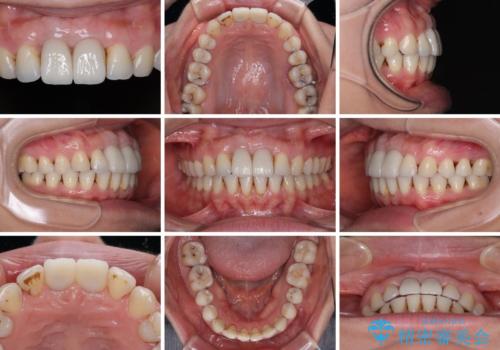

前歯の見た目はもちろん、出血や腫脹のない健全な前歯の状態を獲得することができました。